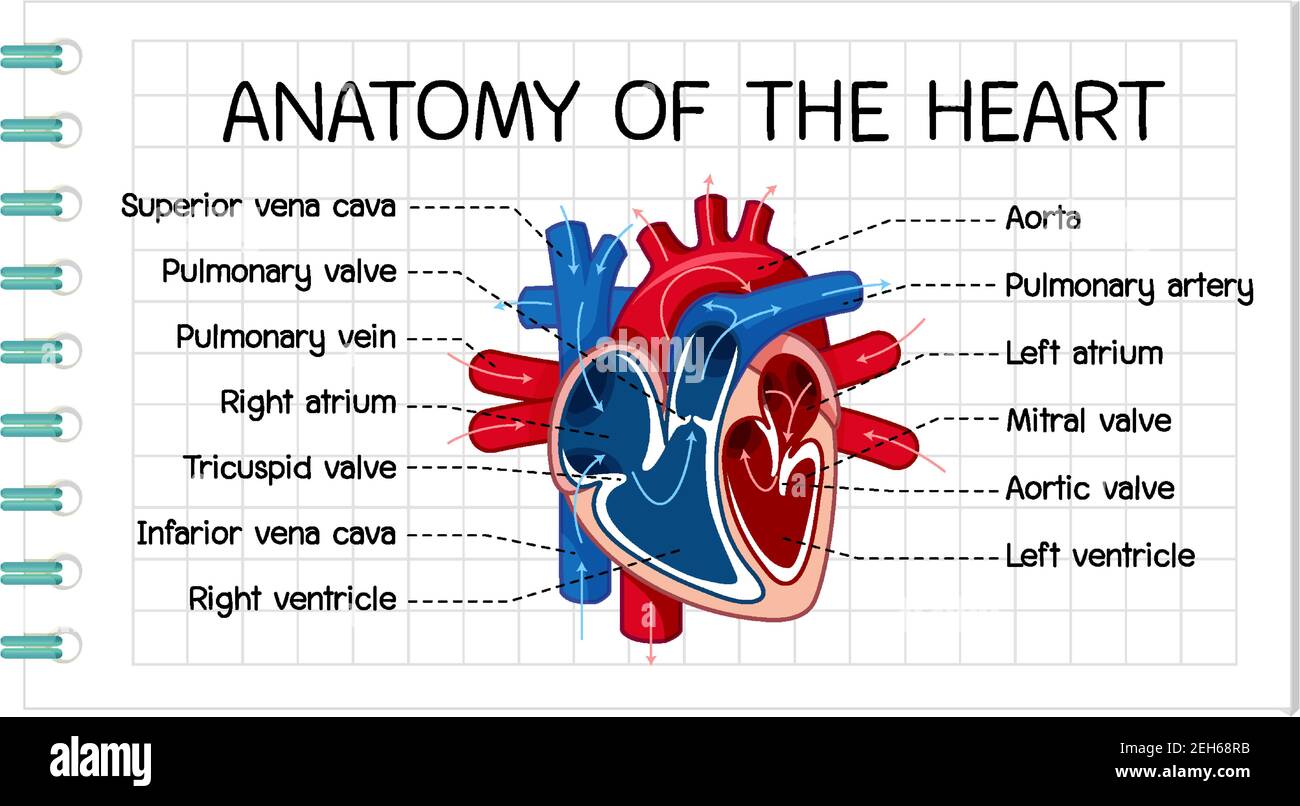

Anatomy of the human heart. Cross sectional diagram of the heart with main parts labeled. Human heart diagram Vector illustration. Educational diagram Stock Vectorhttps://www.alamy.com/image-license-details/?v=1https://www.alamy.com/anatomy-of-the-human-heart-cross-sectional-diagram-of-the-heart-with-main-parts-labeled-human-heart-diagram-vector-illustration-educational-diagram-image551609872.html

Anatomy of the human heart. Cross sectional diagram of the heart with main parts labeled. Human heart diagram Vector illustration. Educational diagram Stock Vectorhttps://www.alamy.com/image-license-details/?v=1https://www.alamy.com/anatomy-of-the-human-heart-cross-sectional-diagram-of-the-heart-with-main-parts-labeled-human-heart-diagram-vector-illustration-educational-diagram-image551609872.htmlRF2R1C00G–Anatomy of the human heart. Cross sectional diagram of the heart with main parts labeled. Human heart diagram Vector illustration. Educational diagram